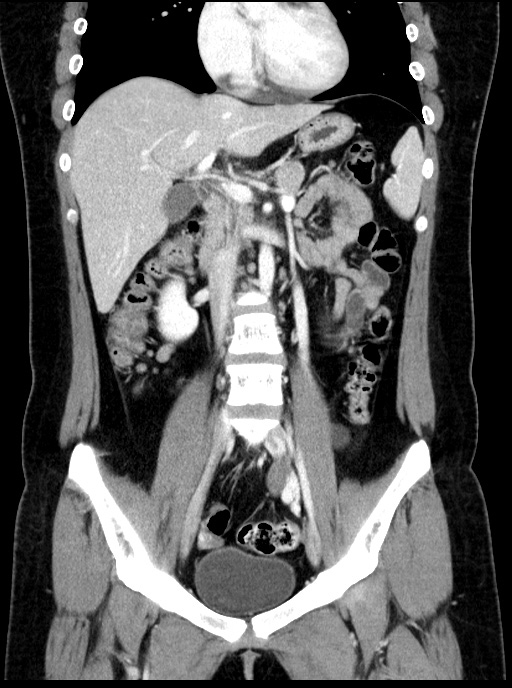

초음파영상에서 보였던 낭성병변은 CT에서는 하행결장과 뚜렷하게 떨어져 있었기에 duplication cyst는 배제할 수 있으며, lymphangitic cyst의 가능성도 떨어져 보입니다. 해당 병변은 Lt. adnexal region에 있는 병변으로 생각됩니다.

관상면 영상에서 해당 병변은 확실히 Lt. adnexal region의 병변입니다. 여기에 더해 좌측 tube가 함께 두꺼워져 있습니다. 이렇게 tubal thickening이 있으면서 주변에 염증반응이나 조영증강소견이 동반되지 않는 경우는 ovary torsion의 가능성을 배제할 수 없습니다.

환자는 대학병원으로 전원해서 수술 후 torsion 소견이 확인되었으며, Lt. adnexal region의 병변의 정체는 조직검사를 했으나 아직 결과가 나오지는 않았다고 합니다.